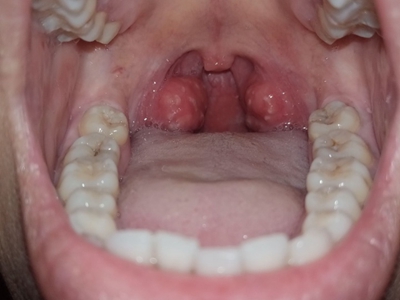

化脓性扁桃体炎扁桃体红肿有白色疙瘩图

化脓性扁桃体炎咽部两侧扁桃体肿大明显,有红枣大小,咽部变狭窄,肿大的黏膜表面有突出的小疙瘩,另外还嵌有形状不规则的白色物质,伴有疼痛,吞咽时更加明显。